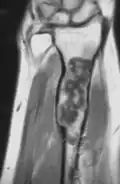

MRI showing enchondromas localized in the lower part of the radius of a 37-year-old patient affected with Ollier disease -

MRI showing enchondromas localized in the lower part of the radius of a 37-year-old patient affected with Ollier disease. -